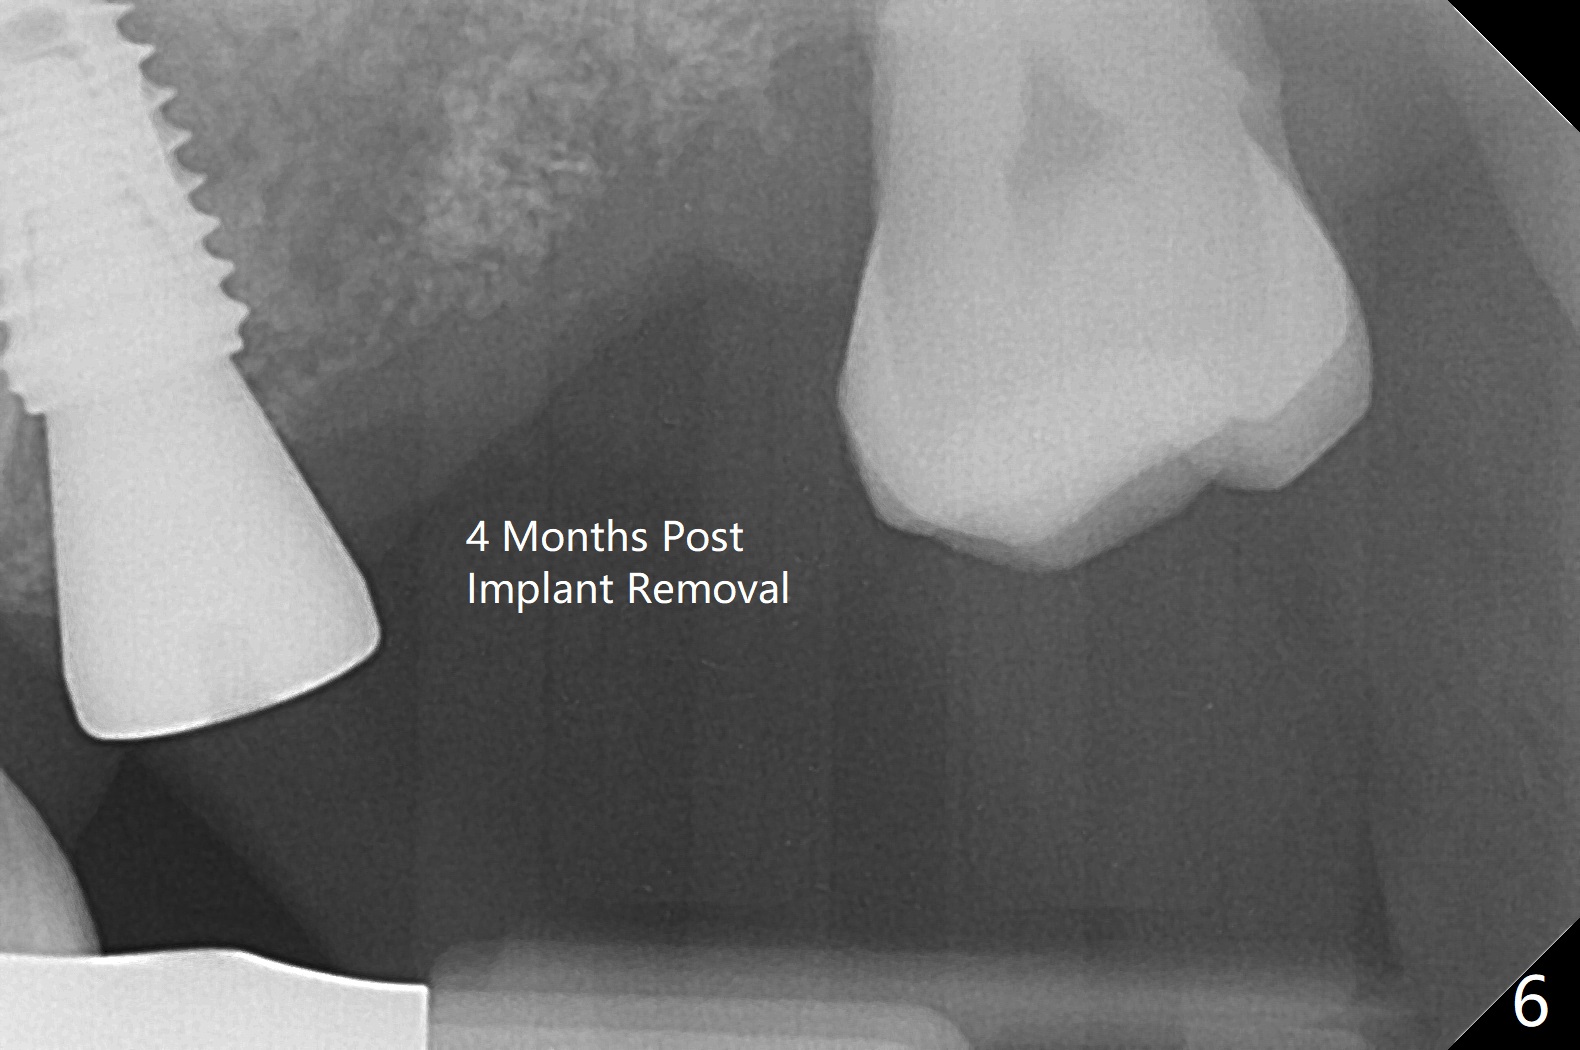

Six days later, "pain is less". Percussion of #13 healing abutment causes headache. There is no mobility at #13 or 14. The buccal gingiva is severely erythematous and edematous at #14. Chlorhexidine irrigation is conducted. After removal of the slightly subgingival healing abutment without pain, a 6x7 mm one is placed with severe pain. After local anesthesia, the implant seems to be mobile. The new abutment is advanced ~ 1 mm (Fig.5). Augmentin is prescribed. One week later there is no sign or symptom of infection. It appears that Augmentin should be prescribed after sinus surgery. The implant at #14 is removed with bone graft 1 month post placement. The graft appears to heal 4 months post implant placement (Fig.6,7 (5 months post placement at #13)).